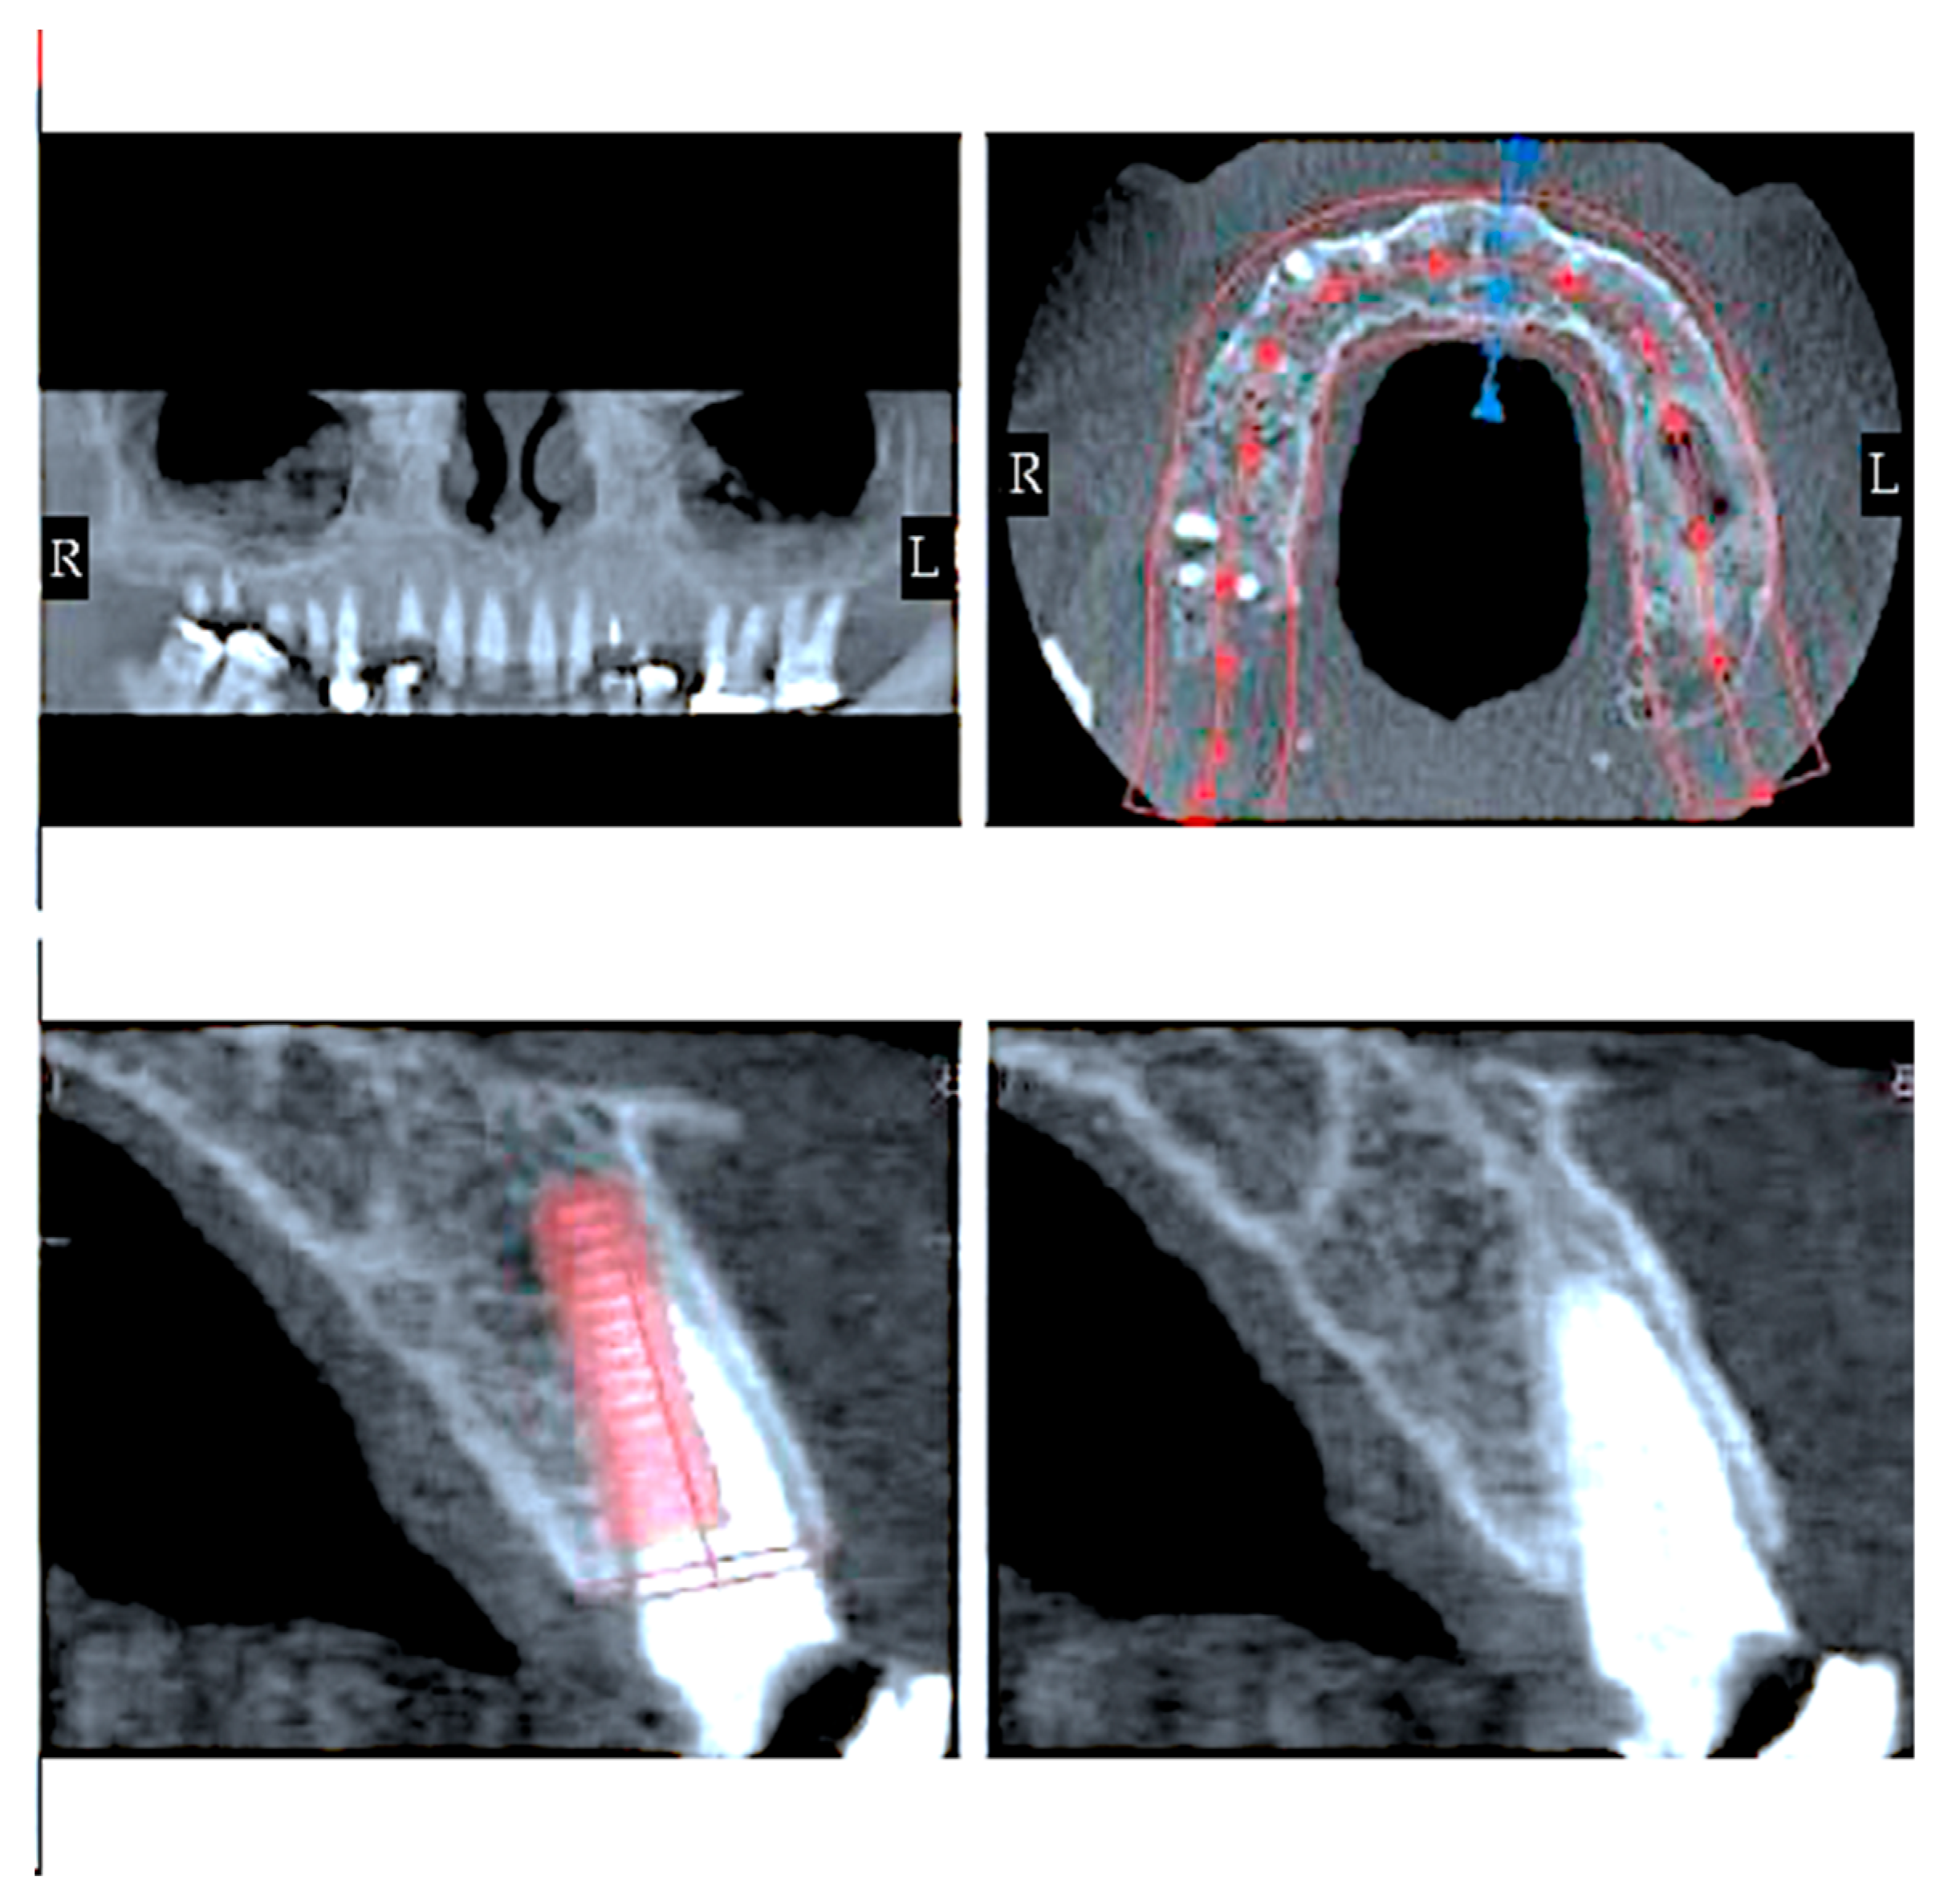

- Surgical intervention (Figure 5).